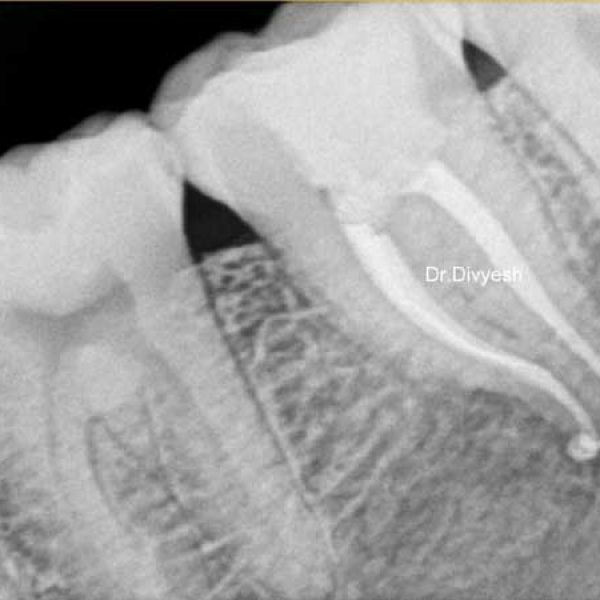

Single Visit Root Canal

Root canal treatment is a dental procedure used to treat infections or damage to the inside of a tooth. with our letest endodontic instruments you will be enjoying pain free root canal treatment in just one appointment only at sanjivnai dental india